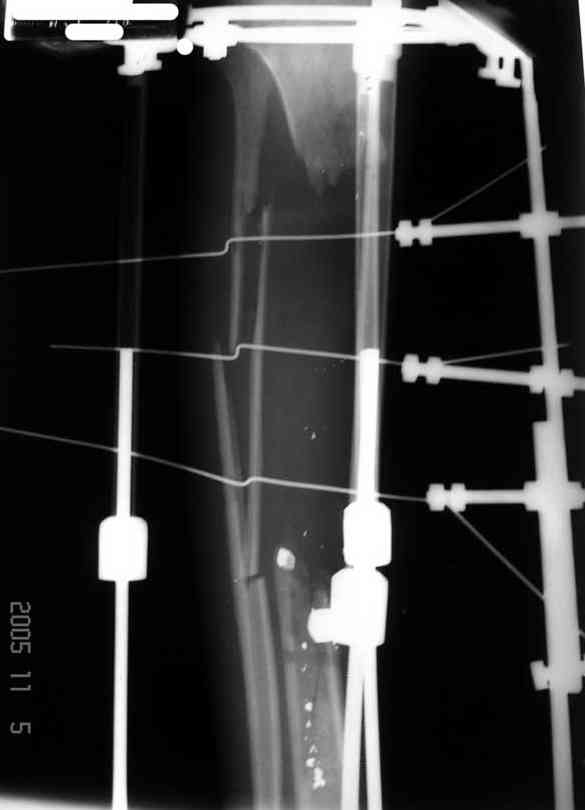

Я думал, что в нижнем отделе голени без мягкотканнего покрытия будет сложно проведения тибиализацию, но твой пример показывает - метод работает даже в таких трудных условиях.

Кстати, как метод использования малоберцовой при дефектах на более высоком отделе большеберцовой, недавно с моим партнерем опубликовали в главе по замещению дефектов в книжке Роберта Росбруха и Светланы Илизаровой по Наружным Фиксаторам.

Правда те мои случаи были сделаны давно, еще в Латинской Америке, и конечно качество исполнения отстает от идеалов, но, несмотря на отсутствие нормальных спиц с упором, метод сработал в свое время.